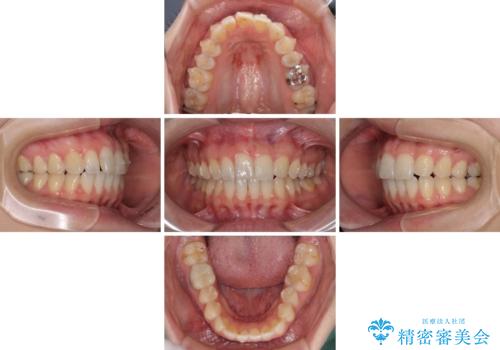

- 矯正治療の後戻りが気になるとのことで来院された患者様です。

上顎の後戻りをインビザライン・ライトで治療することとしました。

上顎のみの治療を希望されたため、咬み合わせをしっかりと改善することはできませんでしたが、審美面が大きく改善され、日常生活の機能面でも不具合を感じることはなく、大変満足していただきました。